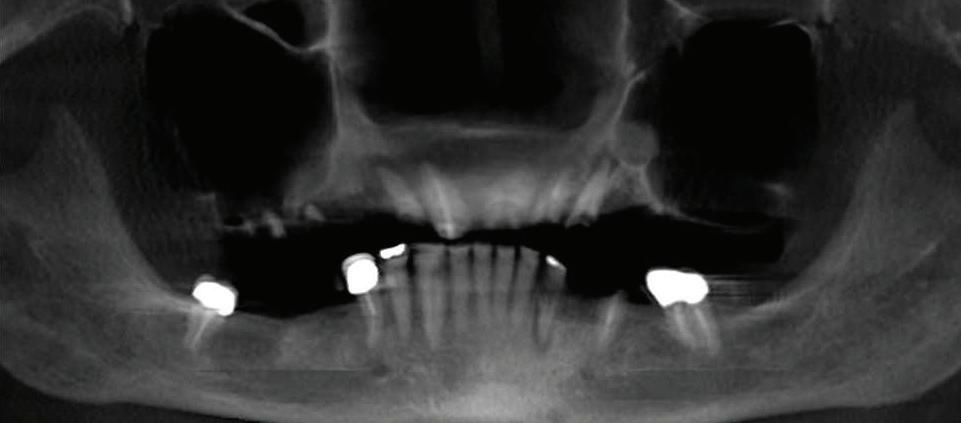

Submitted By Sivakumar Sreenivasan, DMD, MDS

Can just four implants replace all of the teeth on the top or the bottom of your mouth? Thanks to advances in dental implant technology, that answer is a resounding yes.

Believe it or not, tooth loss is extremely common among adults, especially as we age. In fact, more than 35 million people in America are missing all of their upper and/or lower teeth. Rather than living with the discomfort and hassles of dentures, many people are opting for what is called “all-onfour” dental implant restoration.

All-On-Four: One Full Arch Of Teeth, Four Dental Implants

A Reason To Smile Again

able technique for replacing teeth, you should first understand what a dental implant is. An implant is a small titanium screw that fits inside your jawbone and replaces the root-part of a missing tooth. Minor surgery is required to insert the implants. Once the implant is in place, a crown is attached to give you a highly realistic-looking and functional prosthetic tooth.

Here’s where it gets really interesting: You do not need a dental implant for each and every one of your missing teeth. All you need is four precisely placed implants on the top of your mouth, and four on the bottom, to restore your full smile. That’s the beauty of the all-on-four. And because the implant is made of titanium, it has the unique ability to fuse to living bone and function as part of it. So eventually, the dental implant becomes part of the jawbone and serves as a strong, long-lasting foundation for your new teeth.

Besides ensuring that your implants are permanently fixed in place,

Thanks to advances in dental implant technology, just four implants can replace all of the teeth on the top or the bottom of your mouth.

this bone fusion has another important benefit: it prevents future bone loss in the jaw. This helps to maintain a more youthful facial structure – and better oral health. But perhaps the biggest surprise about the all-on-four is how quickly it can transform your life.

At your All-On-Four consultation, you’ll receive a 3D CT Scan. This scan will help determine if you need implants and assist your doctors in creating your treatment plan. So if you want to learn more about dental implants, simply schedule a consultation with an All-On-Four provider. It’s the best way to find out how dental implants can change your life.